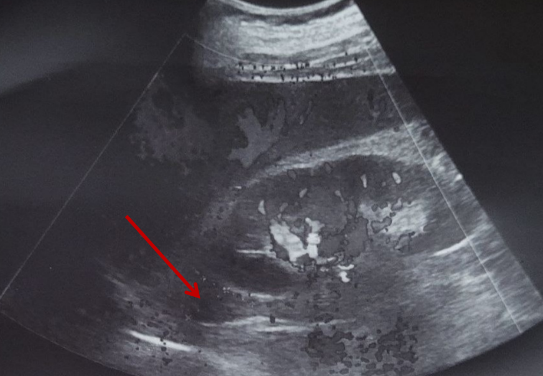

УЗИ экстракраниального отдела брахиоцефальных артерий (рисунок 5 а, б). Позвоночная артерия интракраниального отдела справа – 51 см/сек, слева – 46 см/сек. Кровоток по подключённым артериям магистральных типа с двух сторон. Внутренняя яремная вена справа: кровоток фазный, проходима, 16 мм. Внутренняя яремная вена слева: кровоток фазный, проходима, 11 мм. Позвоночные вены и подключичные вены проходимы с двух сторон. Слева в устье внутренней сонной артерии лоцируется локальная гиперэхогенная атеросклеротическая бляшка, стеноз до 10 %. Мягкая непрямолинейность позвоночных артерий с двух сторон.

а

б

Рис. 5. УЗИ брахиоцефальных артерий. 1 – внутренняя яремная вена без патологических изменений; 2 – общая сонная артерия без патологических изменений; 3 – позвоночная артерия без патологических изменений

Fig. 5. Ultrasound of the brachiocephalic arteries. 1 – internal jugular vein without pathological changes; 2 – common carotid artery without pathological changes; 3 – vertebral artery without pathological changes

Заключение. Комплекс интима-медиа незначительно утолщен, уплотнен. Гемодинамически значимых стенозов экстракраниальных артерий нет. Линейные скоростные показатели кровотока в пределах возрастной нормы.